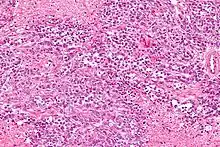

- Elevated 1,25(OH)2D (see calcitriol under Vitamin D) levels (e.g. sarcoidosis and other granulomatous diseases such as tuberculosis, berylliosis, histoplasmosis, Crohn's disease, and granulomatosis with polyangiitis)